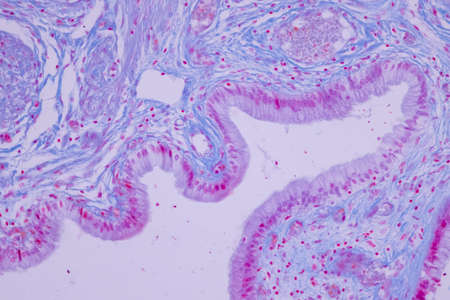

Ovarian cancer, light micrograph, photo under microscope. Photograph shows a fragment of a cancerous tumor in the female ovary. Selective focus